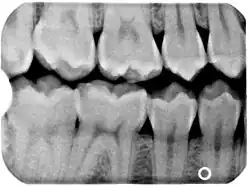

Bissflügelaufnahme rechts